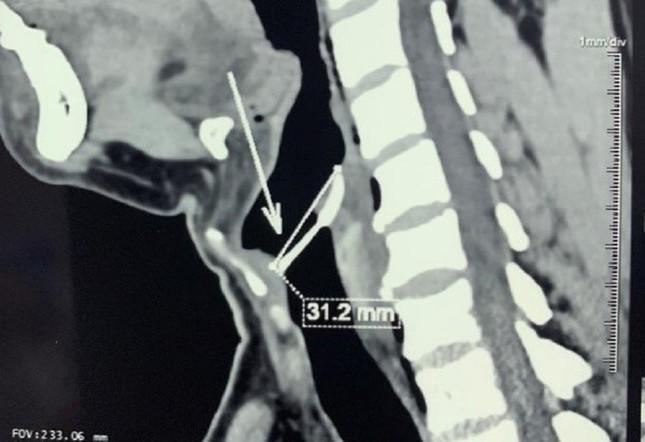

Chiếc xương cá dài hơn 3cm ghim vào thanh quản của bệnh nhân sau khi hóc sặc

Tại đây, qua thăm khám, nội soi hạ họng thanh quản cho bệnh nhân, bác sĩ phát hiện dị vật đã ghim chặt ở thanh môn. Bệnh nhân được chụp CT-scan vùng cổ và ngực thì phát hiện chiếc xương cá ghim vào dây thanh và sụn phễu, tràn khí vùng kế cận, rách niêm mạc xoang.

Chiếc xương cá có chiều dài hơn 3,5cm đã được ê kíp bác sĩ gắp ra ngoài thành công. Ngay sau phẫu thuật bệnh nhân giảm triệu chứng nuốt đau, khàn tiếng rõ rệt, sức khoẻ người bệnh đang bình phục tốt.